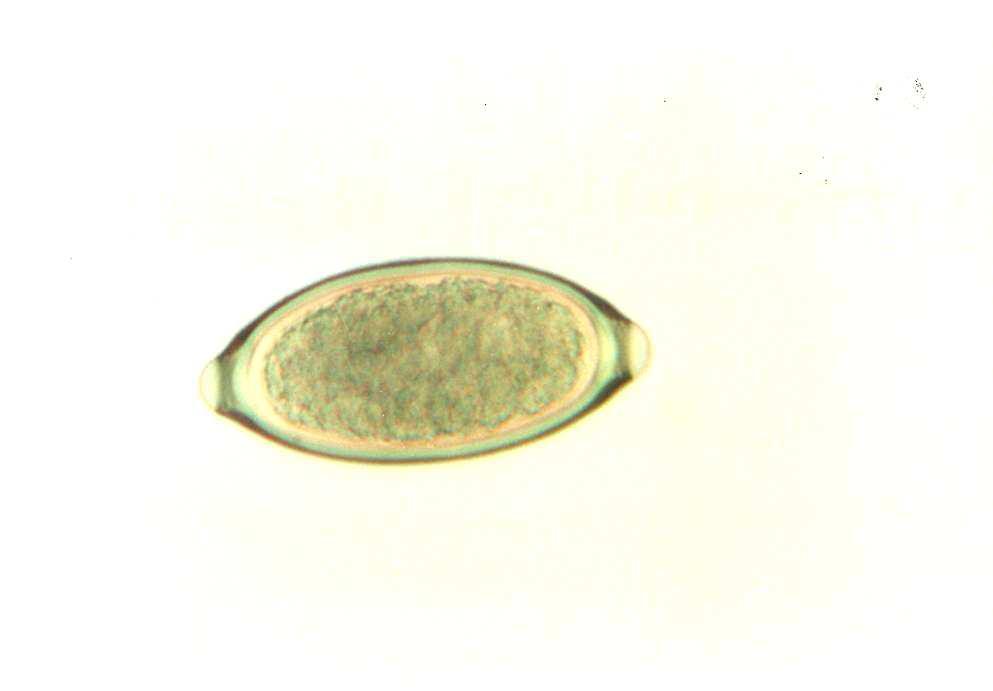

Vajíčko parazitického červa

(Trichuris sp.)

Světlé pole, obj. x20/0.40 |